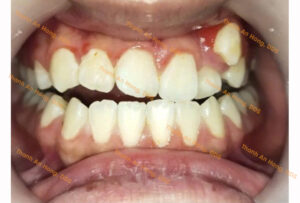

HÌNH ẢNH THỰC TẾ

Chỉnh cắn ngược